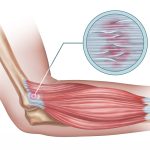

Understanding Hip Osteoporosis: What You Need to Know Tennis Elbow: Causes, Symptoms, and Physiotherapy Treatment Options

Tennis Elbow: Causes, Symptoms, and Physiotherapy Treatment Options Meniscus Injury: What It Is and How Physiotherapy Can Help